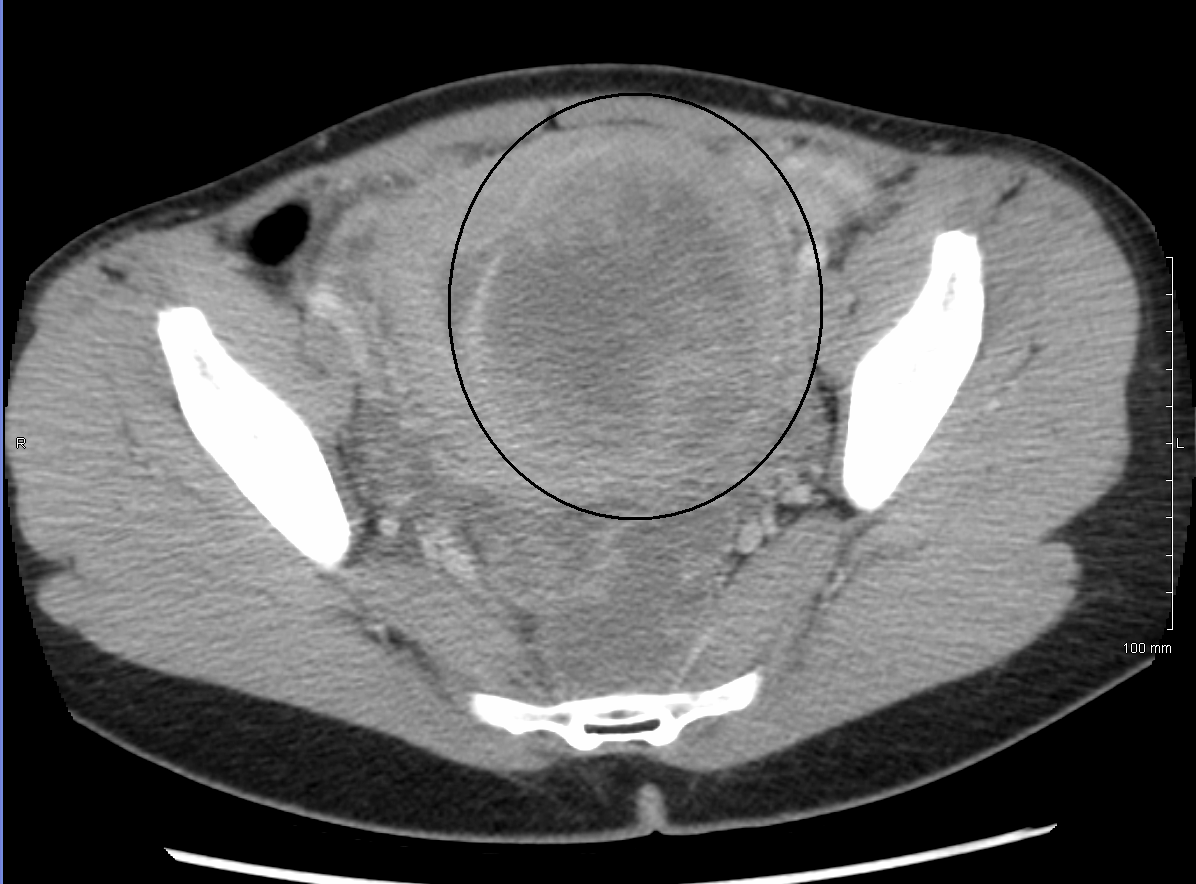

초음파 검사, MRI, 자궁경을 통해 자궁근종을 진단한다. 특히 MRI는 많은 정보를 제공한다. 자궁근종은 T1 강조 영상(T1WI)에서 저신호 또는 등신호, T2 강조 영상(T2WI)에서 저신호를 보이는 것이 일반적이다. 그러나 자궁근종 내 혈액 순환 장애로 인해 충혈, 유리화, 낭포화, 석회화, 지방 변성, 괴사 등 다양한 이차적 변화가 발생하여 다양한 신호 강도를 보일 수 있다. 종양 직경이 8cm를 초과하면 악성 종양일 가능성을 고려해야 한다.

골반 검사와 초음파 검사만으로도 대부분의 환자에게서 자궁근종을 진단하기에 충분하다. 초음파 검사 결과가 불분명할 경우, 자기 공명 영상(MRI)을 통해 대부분 자궁근종 진단을 확진할 수 있다. 또한 MRI는 비정형 영상 특징을 보이는 양성 자궁근종과 변이 성장 패턴을 보이는 자궁근종을 식별할 수 있다. MRI는 자궁근종과 유사하게 보이거나 환자의 증상에 기여할 수 있는 다른 자궁 질환(예: 자궁선근증, 자궁내막 용종, 자궁내막암) 및 자궁 외 질환(예: 양성 및 악성 난소 종양, 자궁내막증)도 식별할 수 있다.[33] 그러나 자궁근종의 작은 비율은 사용 가능한 모든 영상 검사(예: 초음파, CT, MRI 및 PET-CT)에서 다른 악성 자궁 종양(예: 평활근육종)과 유사하게 보일 수 있다.[33]자궁벽의 악성 종양(예: 평활근육종)은 매우 드물다. 양성 근종보다 악성 자궁 종양을 시사하는 소견으로는 빠르거나 예상치 못한 성장(특히 폐경기 이후), 자궁내막 줄무늬의 중단/소실, 림프절 비대, 인접 장기 침범 및 원격 장기(예: 폐) 전이 등이 있다. 악성을 시사하는 MRI 소견으로는 결절성/불분명한 종양 경계, 고형 종양 성분의 중간/높은 T2 강조 신호 강도, 아급성 출혈과 일치하는 높은 신호 T1 강조 시퀀스 영역, 종양의 고형 부분의 미세한/흐릿한 조영 증강, 확산 강조 영상(DWI)에서 확산 제한 등이 있다.[33] 생검은 드물게 수행되며, 수행하더라도 진단적이지 않은 경우가 많다. 초음파 및 MRI 영상 검사 후 진단이 불확실한 경우 일반적으로 수술이 권장된다.[34]

골반 검사와 초음파 검사만으로도 대부분의 환자에게서 자궁근종을 진단하기에 충분하다. 초음파 검사 결과가 불분명할 경우, 자기 공명 영상(MRI)을 통해 대부분 자궁근종 진단을 확진할 수 있다.[33] 초음파 검사, 자기 공명 영상(MRI), 자궁경을 통해 관찰한다.4. 3. 자기공명영상(MRI)

골반 검사와 초음파 검사만으로도 대부분 자궁근종 진단이 가능하지만, 초음파 검사 결과가 불분명한 경우 자기공명영상(MRI)을 통해 확진할 수 있다.[33] MRI는 비정형적인 양성 자궁근종과 변이 성장 패턴을 보이는 자궁근종을 식별할 수 있다.[33] 또한, 자궁근종과 유사하게 보이거나 증상에 영향을 줄 수 있는 다른 자궁 및 자궁 외 질환(예: 자궁선근증, 자궁내막 용종, 자궁내막암, 양성 및 악성 난소 종양, 자궁내막증)을 식별하는 데에도 도움이 된다.[33]하지만 일부 자궁근종은 사용 가능한 모든 영상 검사(예: 초음파, CT, MRI, PET-CT)에서 다른 악성 자궁 종양(예: 평활근육종)과 유사하게 보일 수 있다.[33] 악성 종양을 시사하는 소견으로는 빠르거나 예상치 못한 성장(특히 폐경기 이후), 자궁내막 줄무늬 중단/소실, 림프절 비대, 인접 장기 침범, 원격 장기(예: 폐) 전이 등이 있다. 악성을 시사하는 MRI 소견으로는 결절성/불분명한 종양 경계, 고형 종양 성분의 중간/높은 T2 강조 신호 강도, 아급성 출혈과 일치하는 높은 신호 T1 강조 시퀀스 영역, 종양 고형 부분의 미세/흐릿한 조영 증강, 확산 강조 영상(DWI)에서 확산 제한 등이 있다.[33]